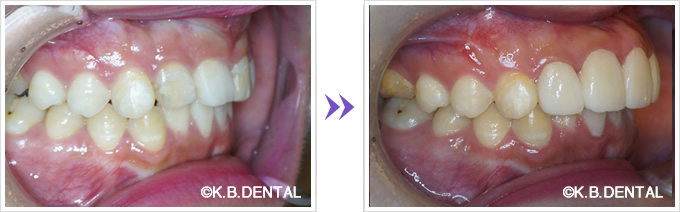

上顎外側骨隆起 症例2(上顎の頬側にできた骨隆起)

笑った時にゴボ口となりやすく、隆起した部分に食物残渣などが生じやすいケースです。静脈麻酔で約1時間半程度要します。

料金

静脈内鎮静法による麻酔代込:約20万円(保険適用外)